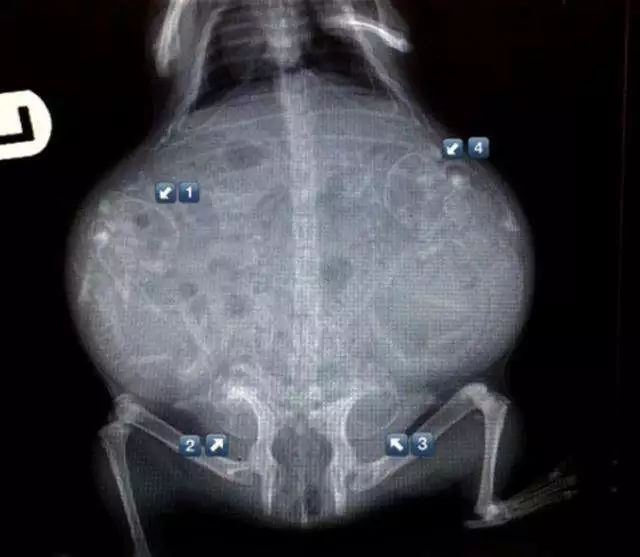

但是超声因为体位问题,对胎儿数量的判断并不精确,漏诊是非常正常的事,如果要确认胎儿数量,还是得靠x光。

在妊娠期的45天左右,用X射线检测能看到胎儿的骨架,进而可以确认胎儿数量。

放心,一次到两次X射线并不会伤害猫妈妈和胎儿。